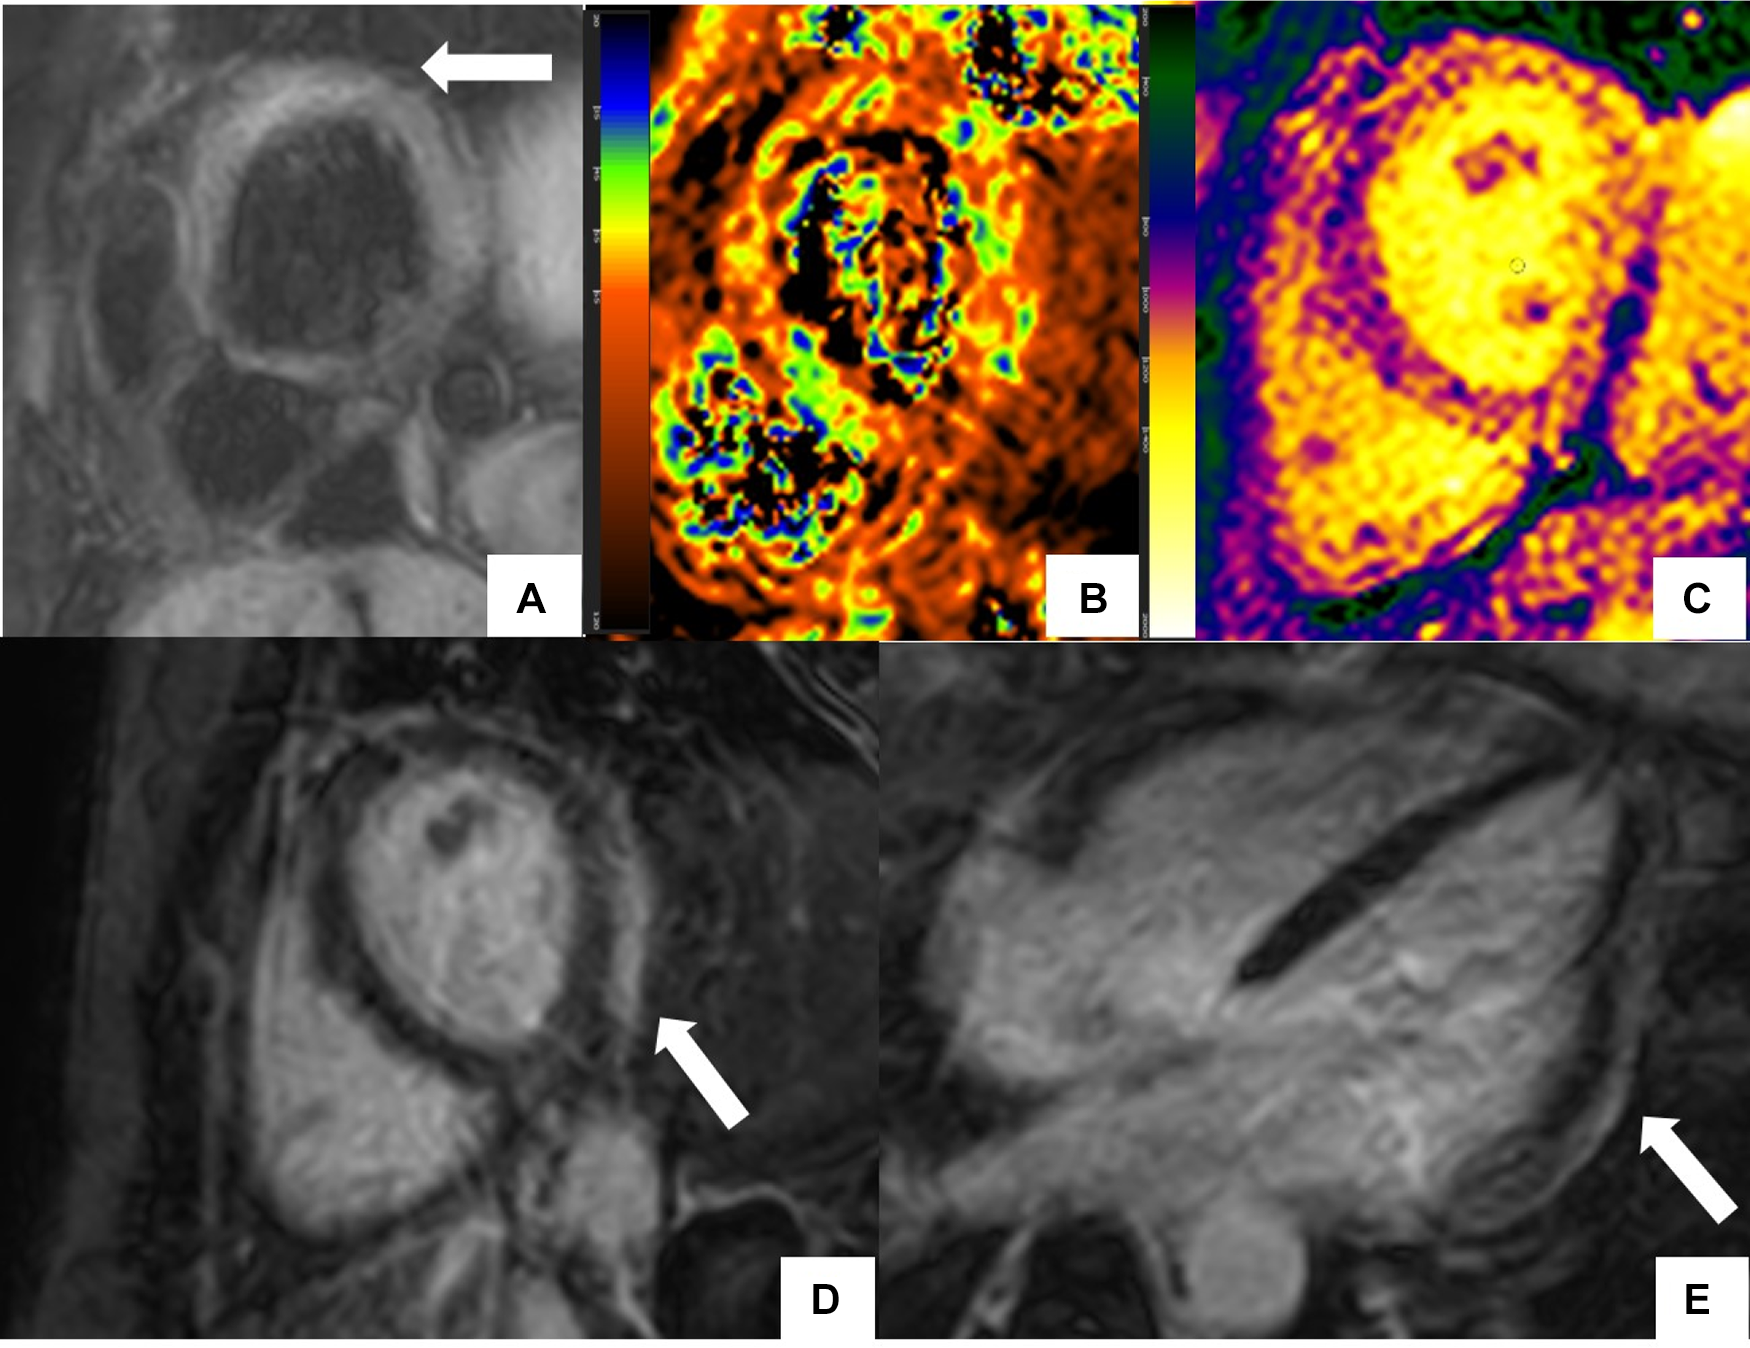

Figure 1

CMR findings in systemic lupus erythematosus (SLE) myopericarditis. 44 year old female with longstanding systemic lupus erythematosus (SLE) and overlap syndrome with premature ventricular contractions and dyspnea on exertion. Cardiac MR (CMR) showed mild biventricular systolic dysfunction with left ventricular ejection fraction (LVEF) of 48% and right ventricular ejection fraction of (RVEF) of 42%. Edema was seen on T2 black blood fat supressed short axis image (A) with elevated T2 value of 72 ms on T2 color map (B) and diffusely increased myocardial native T1 value of 1,134 ms on native T1 color map (C) On short-axis and 4-chamber late gadolinium enhancement phase-sensitive inversion recovery (LGE- PSIR) image, subepicardial hyperenhancement was seen within the entire inferolateral wall (D,E respectively). Constellation of findings were consistent with cardiac involvement in SLE with an acute inflammatory component (42). Pericardial thickening with diffuse LGE and increased T2 signal in the basal anterior wall away from LGE suggested acute on chronic pericarditis. No pericardial effusion was seen.